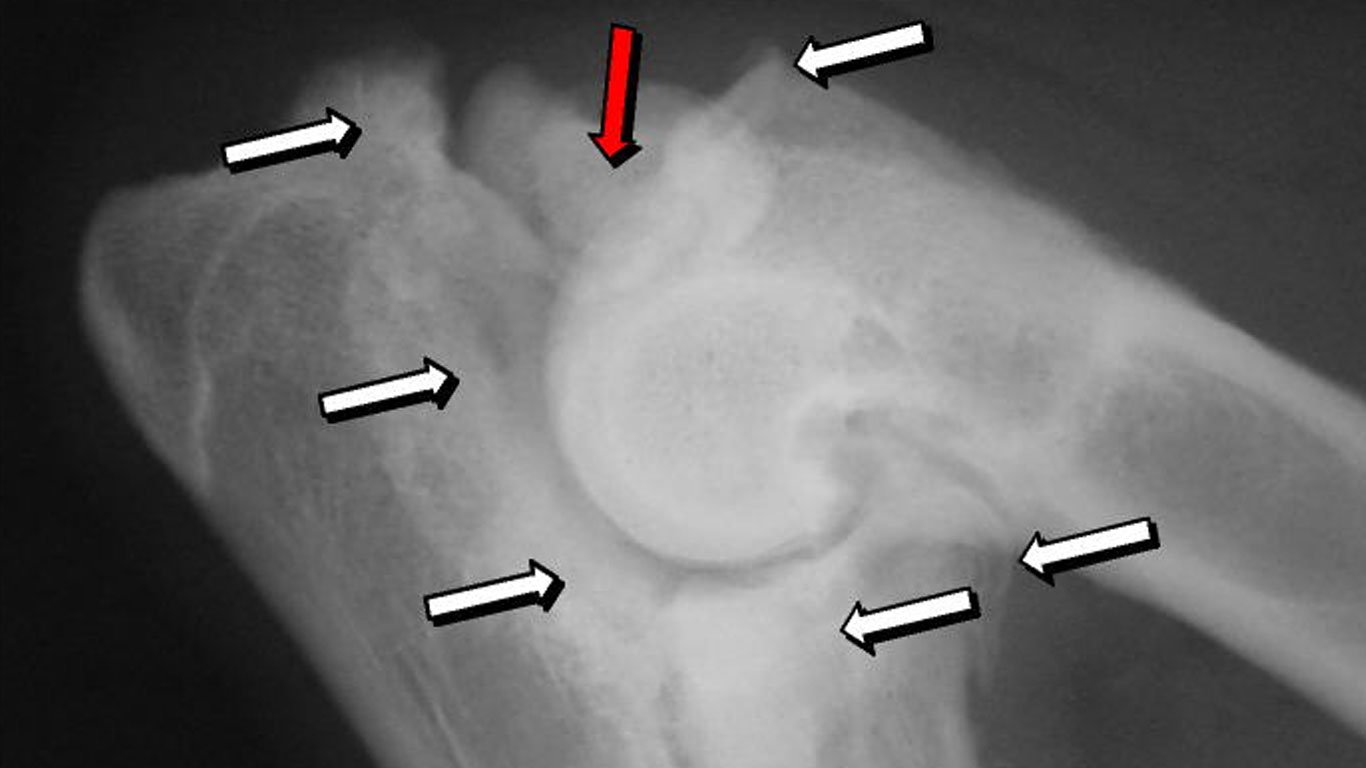

Die Ellenbogendysplasie (ED) ist eine Erkrankung, bei der das Ellenbogengelenk des Hundes nicht korrekt entwickelt ist. Das[…]